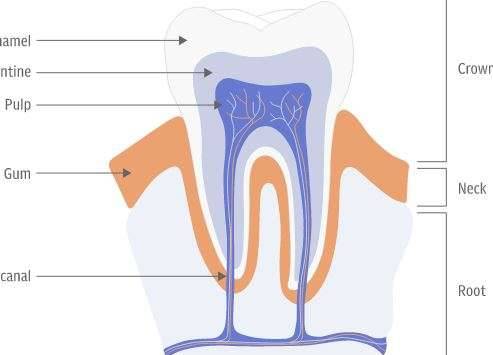

▼「Tideglusib」原先是一种用于治疗阿兹海默症的药物,但是来自伦敦国王大学(King’s College London)的研究团队日前却发现,它可以让我们牙髓中的干细胞活化起来,大大地增强了牙齿的自然复原能力,换句话说,以后我们可以无需补牙,就能够修复好被蛀洞的牙齿了。

▼然而许多人都没有发现的是,我们的牙齿也有属于自己的生理机能,它本身就有着一定的修复能力,只是它仅能够自行复原象牙质般的小裂缝,不足以去抵御修复蛀牙。不过研究人员日前就发现,只要藉由Tideglusib来活化牙齿中的干细胞,强化自然修复能力,那我们的牙齿就有机会可以自行复原蛀洞了。